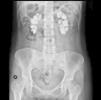

The electrocardiogram showed sinus rhythm with an ST elevation of 1mm in all leads. The chest X-ray was normal. In plain abdominal X-ray, there were extensive bilateral renal calcifications (Fig. 1). After correcting the hypocalcaemia, hypomagnesaemia and metabolic acidosis, the patient was discharged, with no significant incidents during admission. Lab test values at discharge were creatinine 3.6mg/dL; sodium 142mmol/l; potassium 4.4mmol/l; pH 7.43; bicarbonate 24.6mmol/l; calcium 8.6mg/dL; corrected calcium ion 1.16mmol/l; phosphorus 2.9, iPTH 103ng/ml and magnesium 1.9mg/dL. Treatment at discharge was: calcium carbonate 2.5g every 8h; calcitriol 0.5 mcg/day; sodium bicarbonate 1g/day and oral potassium and magnesium supplements.